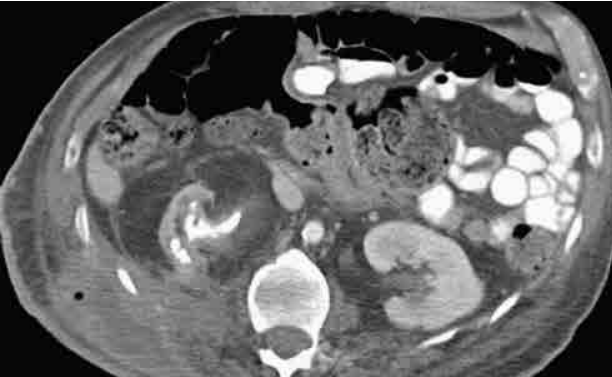

Mulher de setenta anos de idade, obesa, portadora de diabetes mellitus e histórico de nefrolitíase dá entrada no pronto-socorro com dor lombar à direita há três dias, febre aferida, diminuição da diurese e mantendo estabilidade hemodinâmica. Foram realizados exames laboratoriais, que evidenciariam o aumento de provas inflamatórias, escórias nitrogenadas e urina tipo 1 infecciosa. Também foi realizada tomografia de abdome e pelve, com contraste endovenoso.

Com base nesse caso hipotético e considerando a avaliação do corte tomográfico na imagem acima, a principal hipótese diagnóstica é